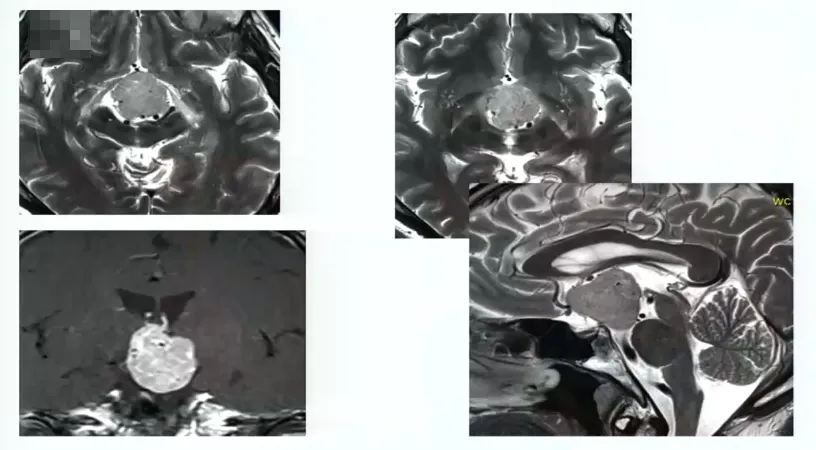

手术病例4:

50岁男性,出现严重视野缺损

图:术前MRI

图:术中核磁辅助手术后,进行术中检查看是否在角落里有残留肿瘤。术中检查及术后核磁均显示肿瘤完全切除。